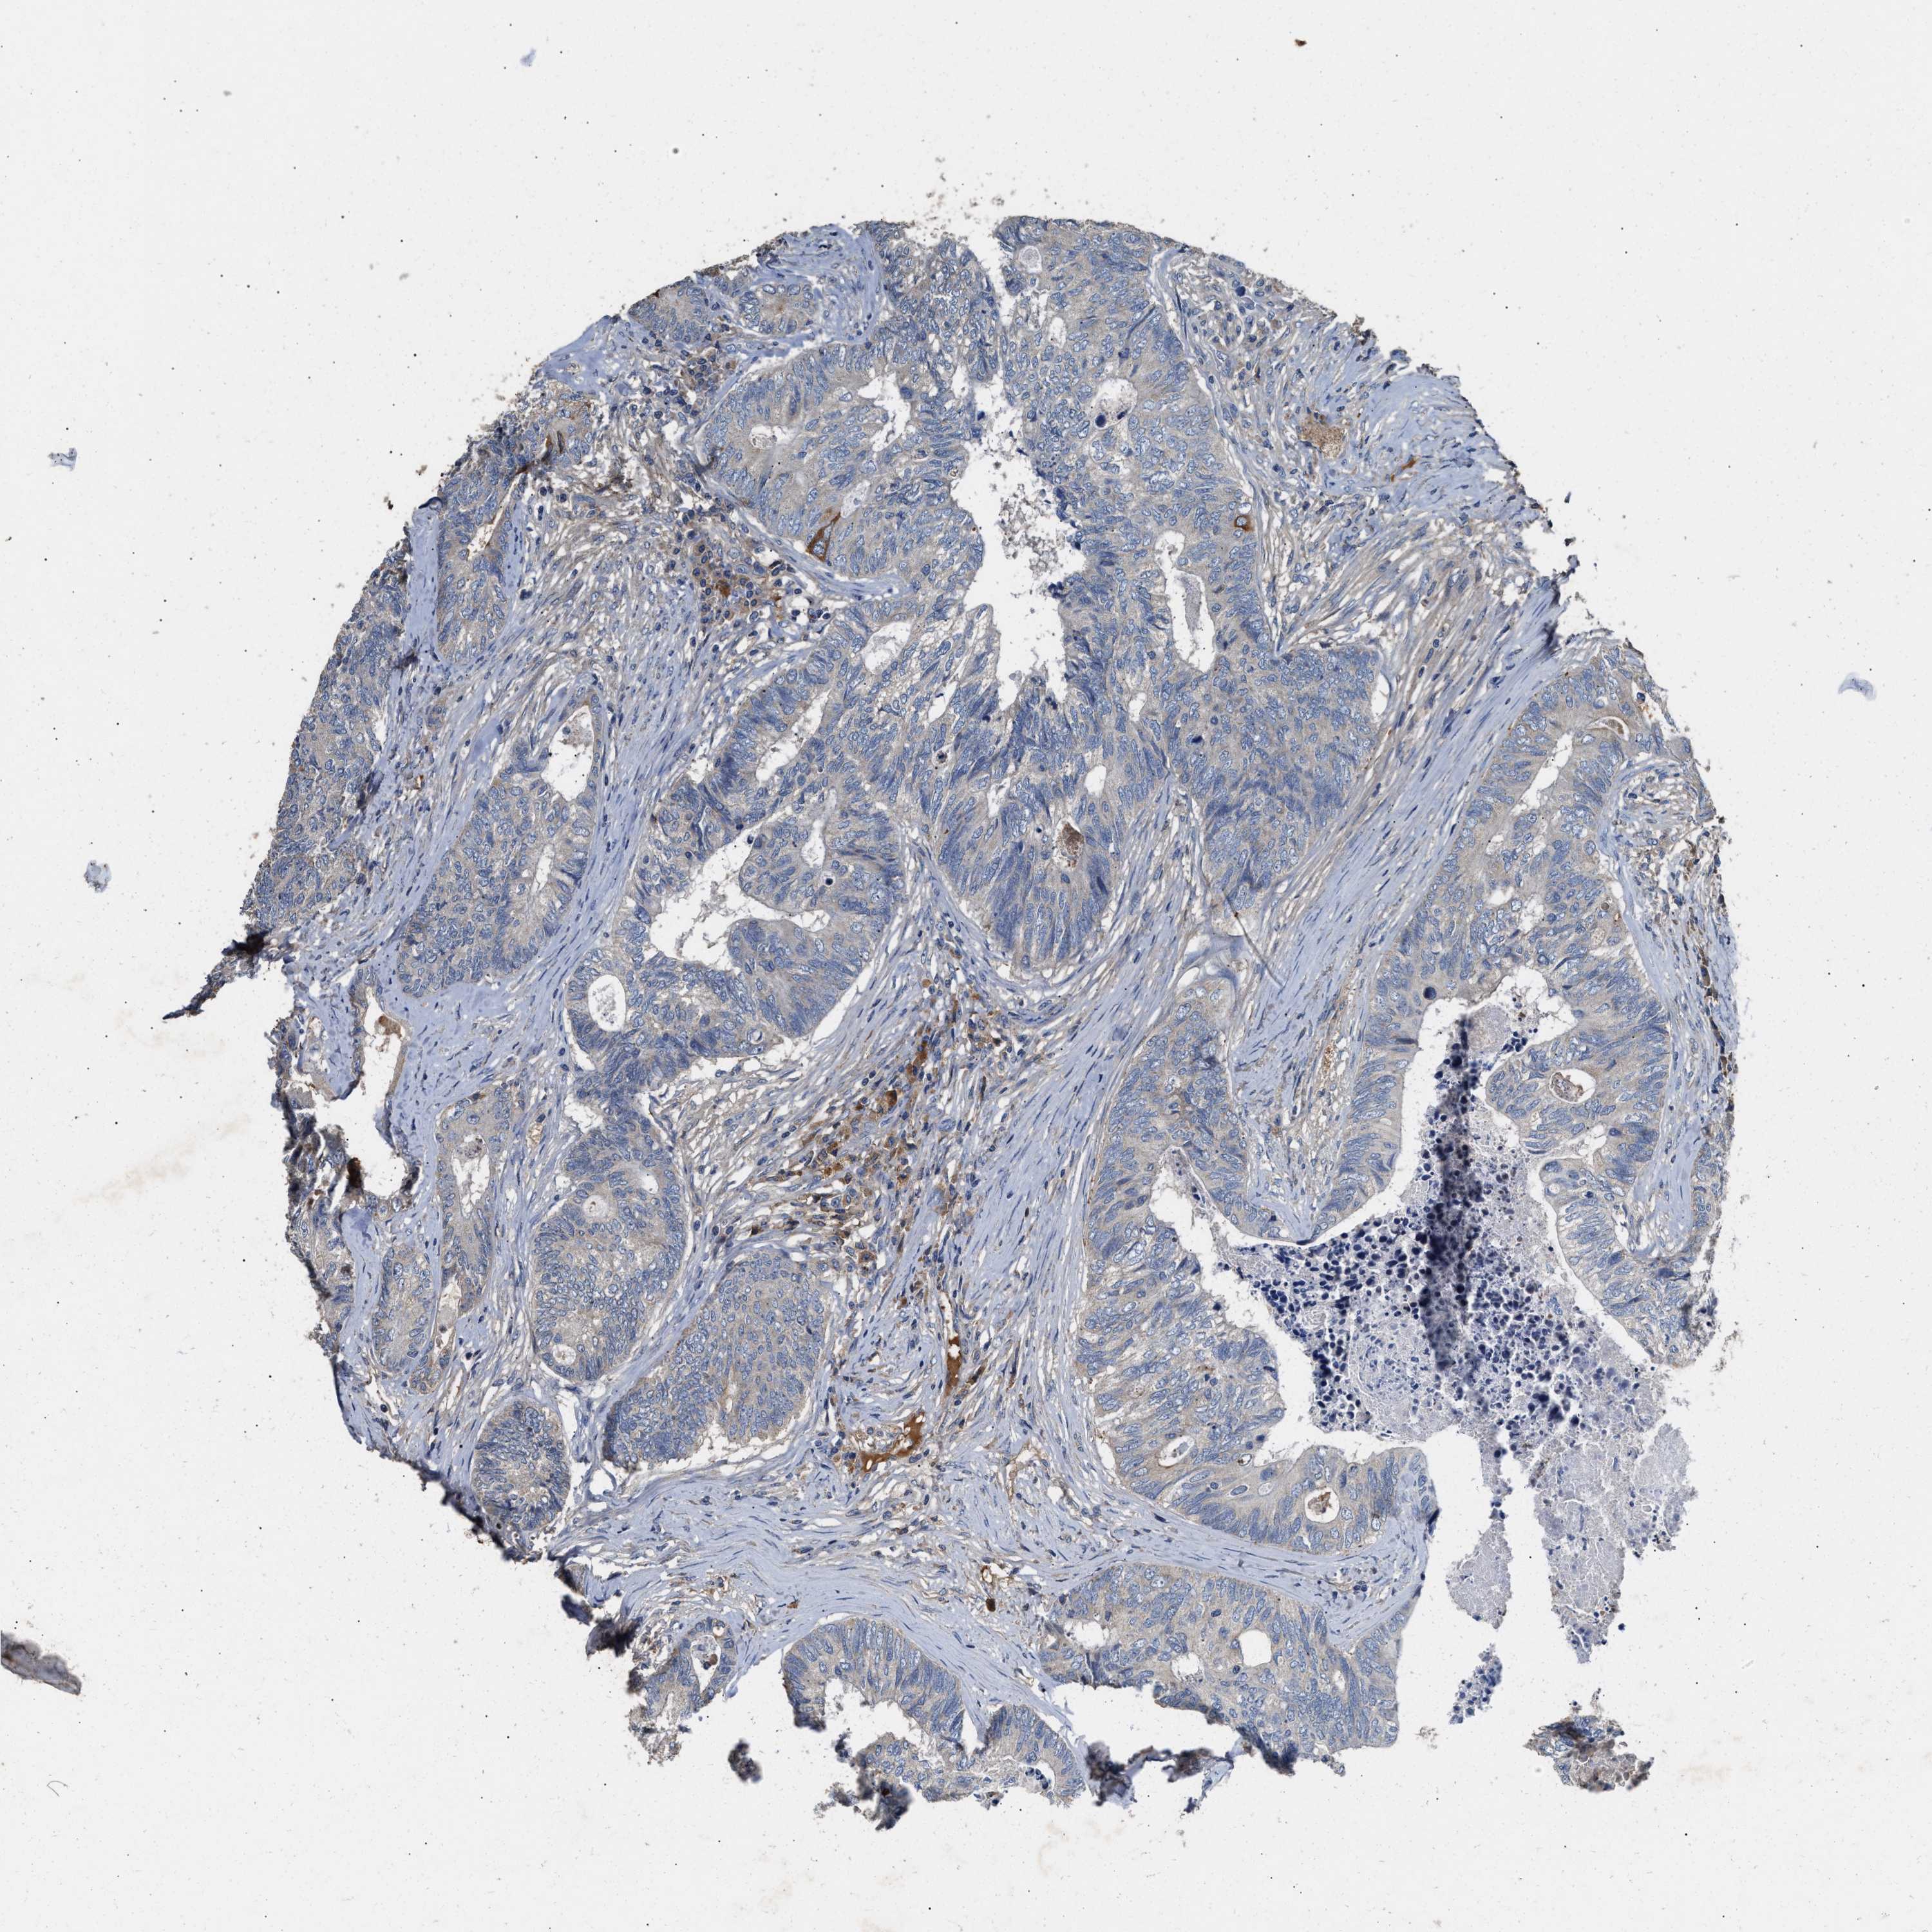

CANCER COLORECTAL CANCER Show tissue menu

Colorectal cancer

Human cancer

Colon adenocarcinoma

RECTUM ADENOCARCINOMA (TCGA) - Interactive survival scatter ploti

C3 is not prognostic in Rectum Adenocarcinoma (TCGA)